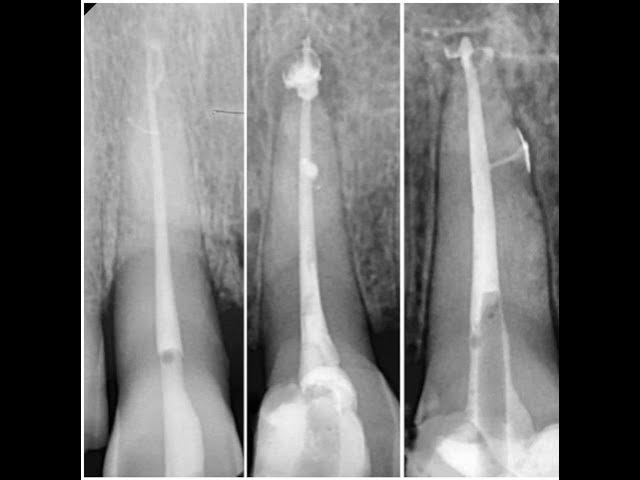

Lateral and Accessory Canals in Endodontics: A Complete Clinical Guide | Dentistry Simplified Ep.3

"In this episode of Dentistry Simplified, we explore lateral and accessory canals in endodontics. Learn their clinical significance, diagnostic challenges, and management strategies with a clear, step-by-step guide. Perfect for dental students and professionals aiming to strengthen their endodontic knowledge. For more resources, visit DentalClinicGuide.com."